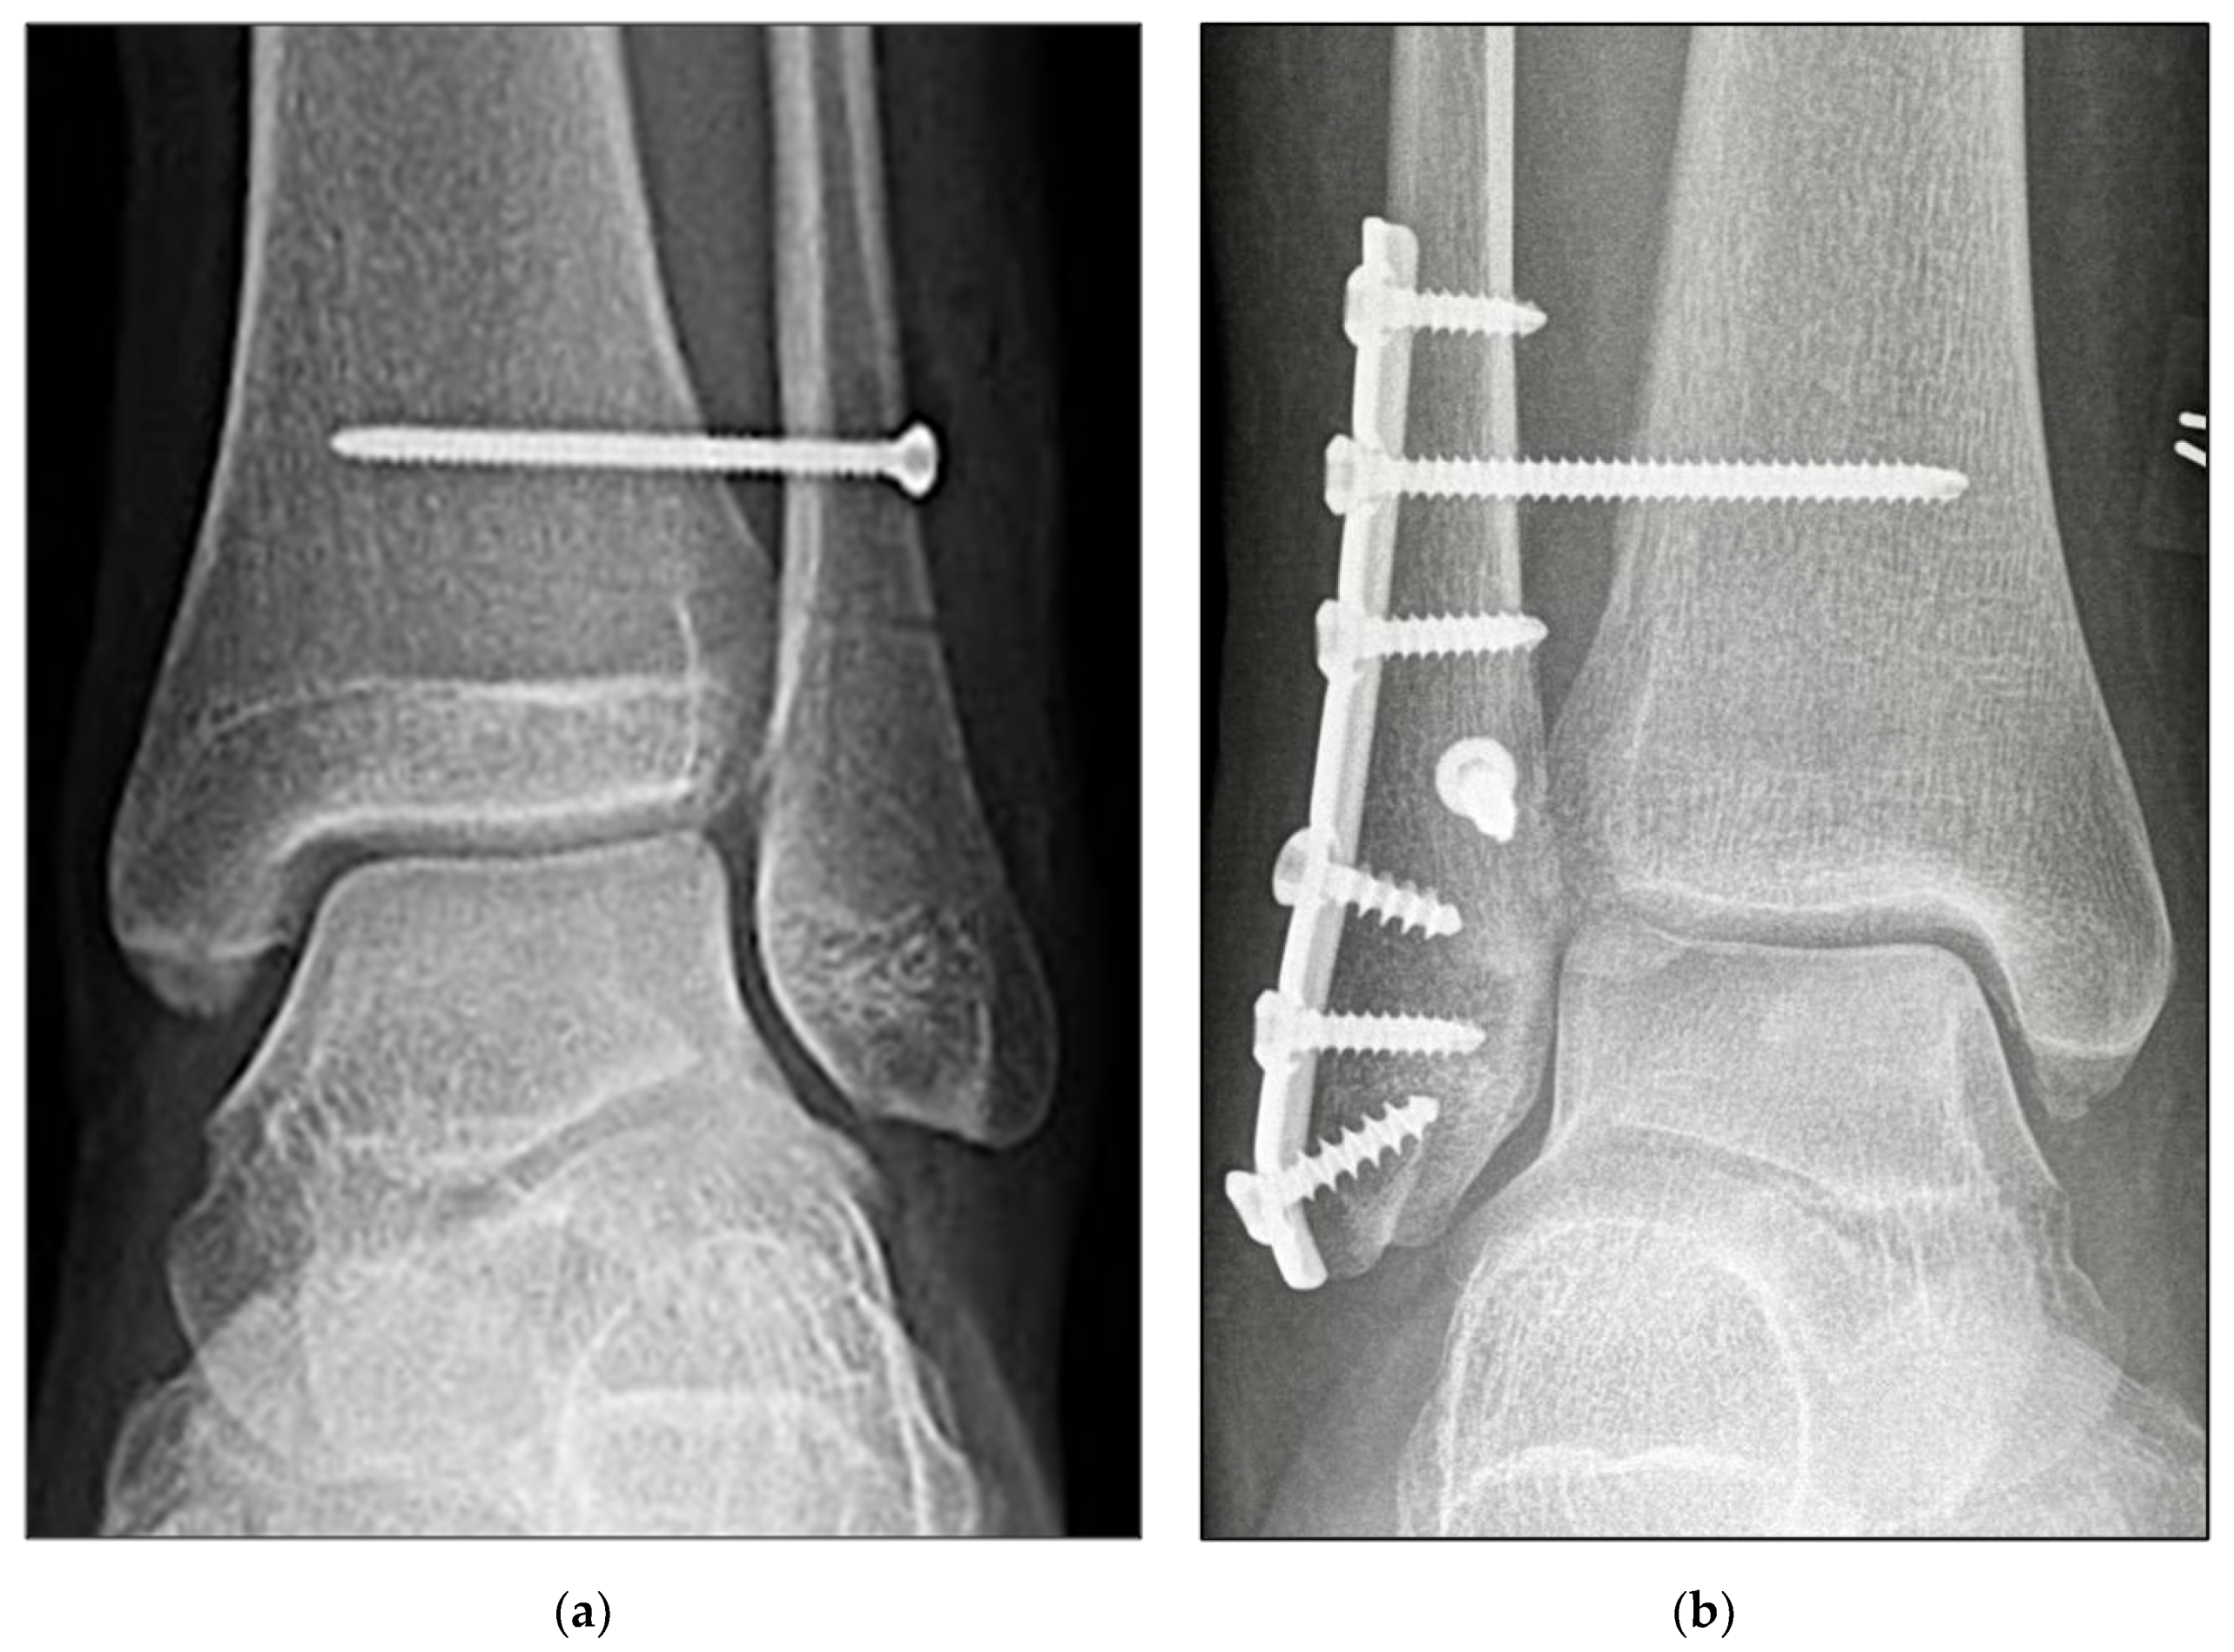

2.3. Surgical Procedure